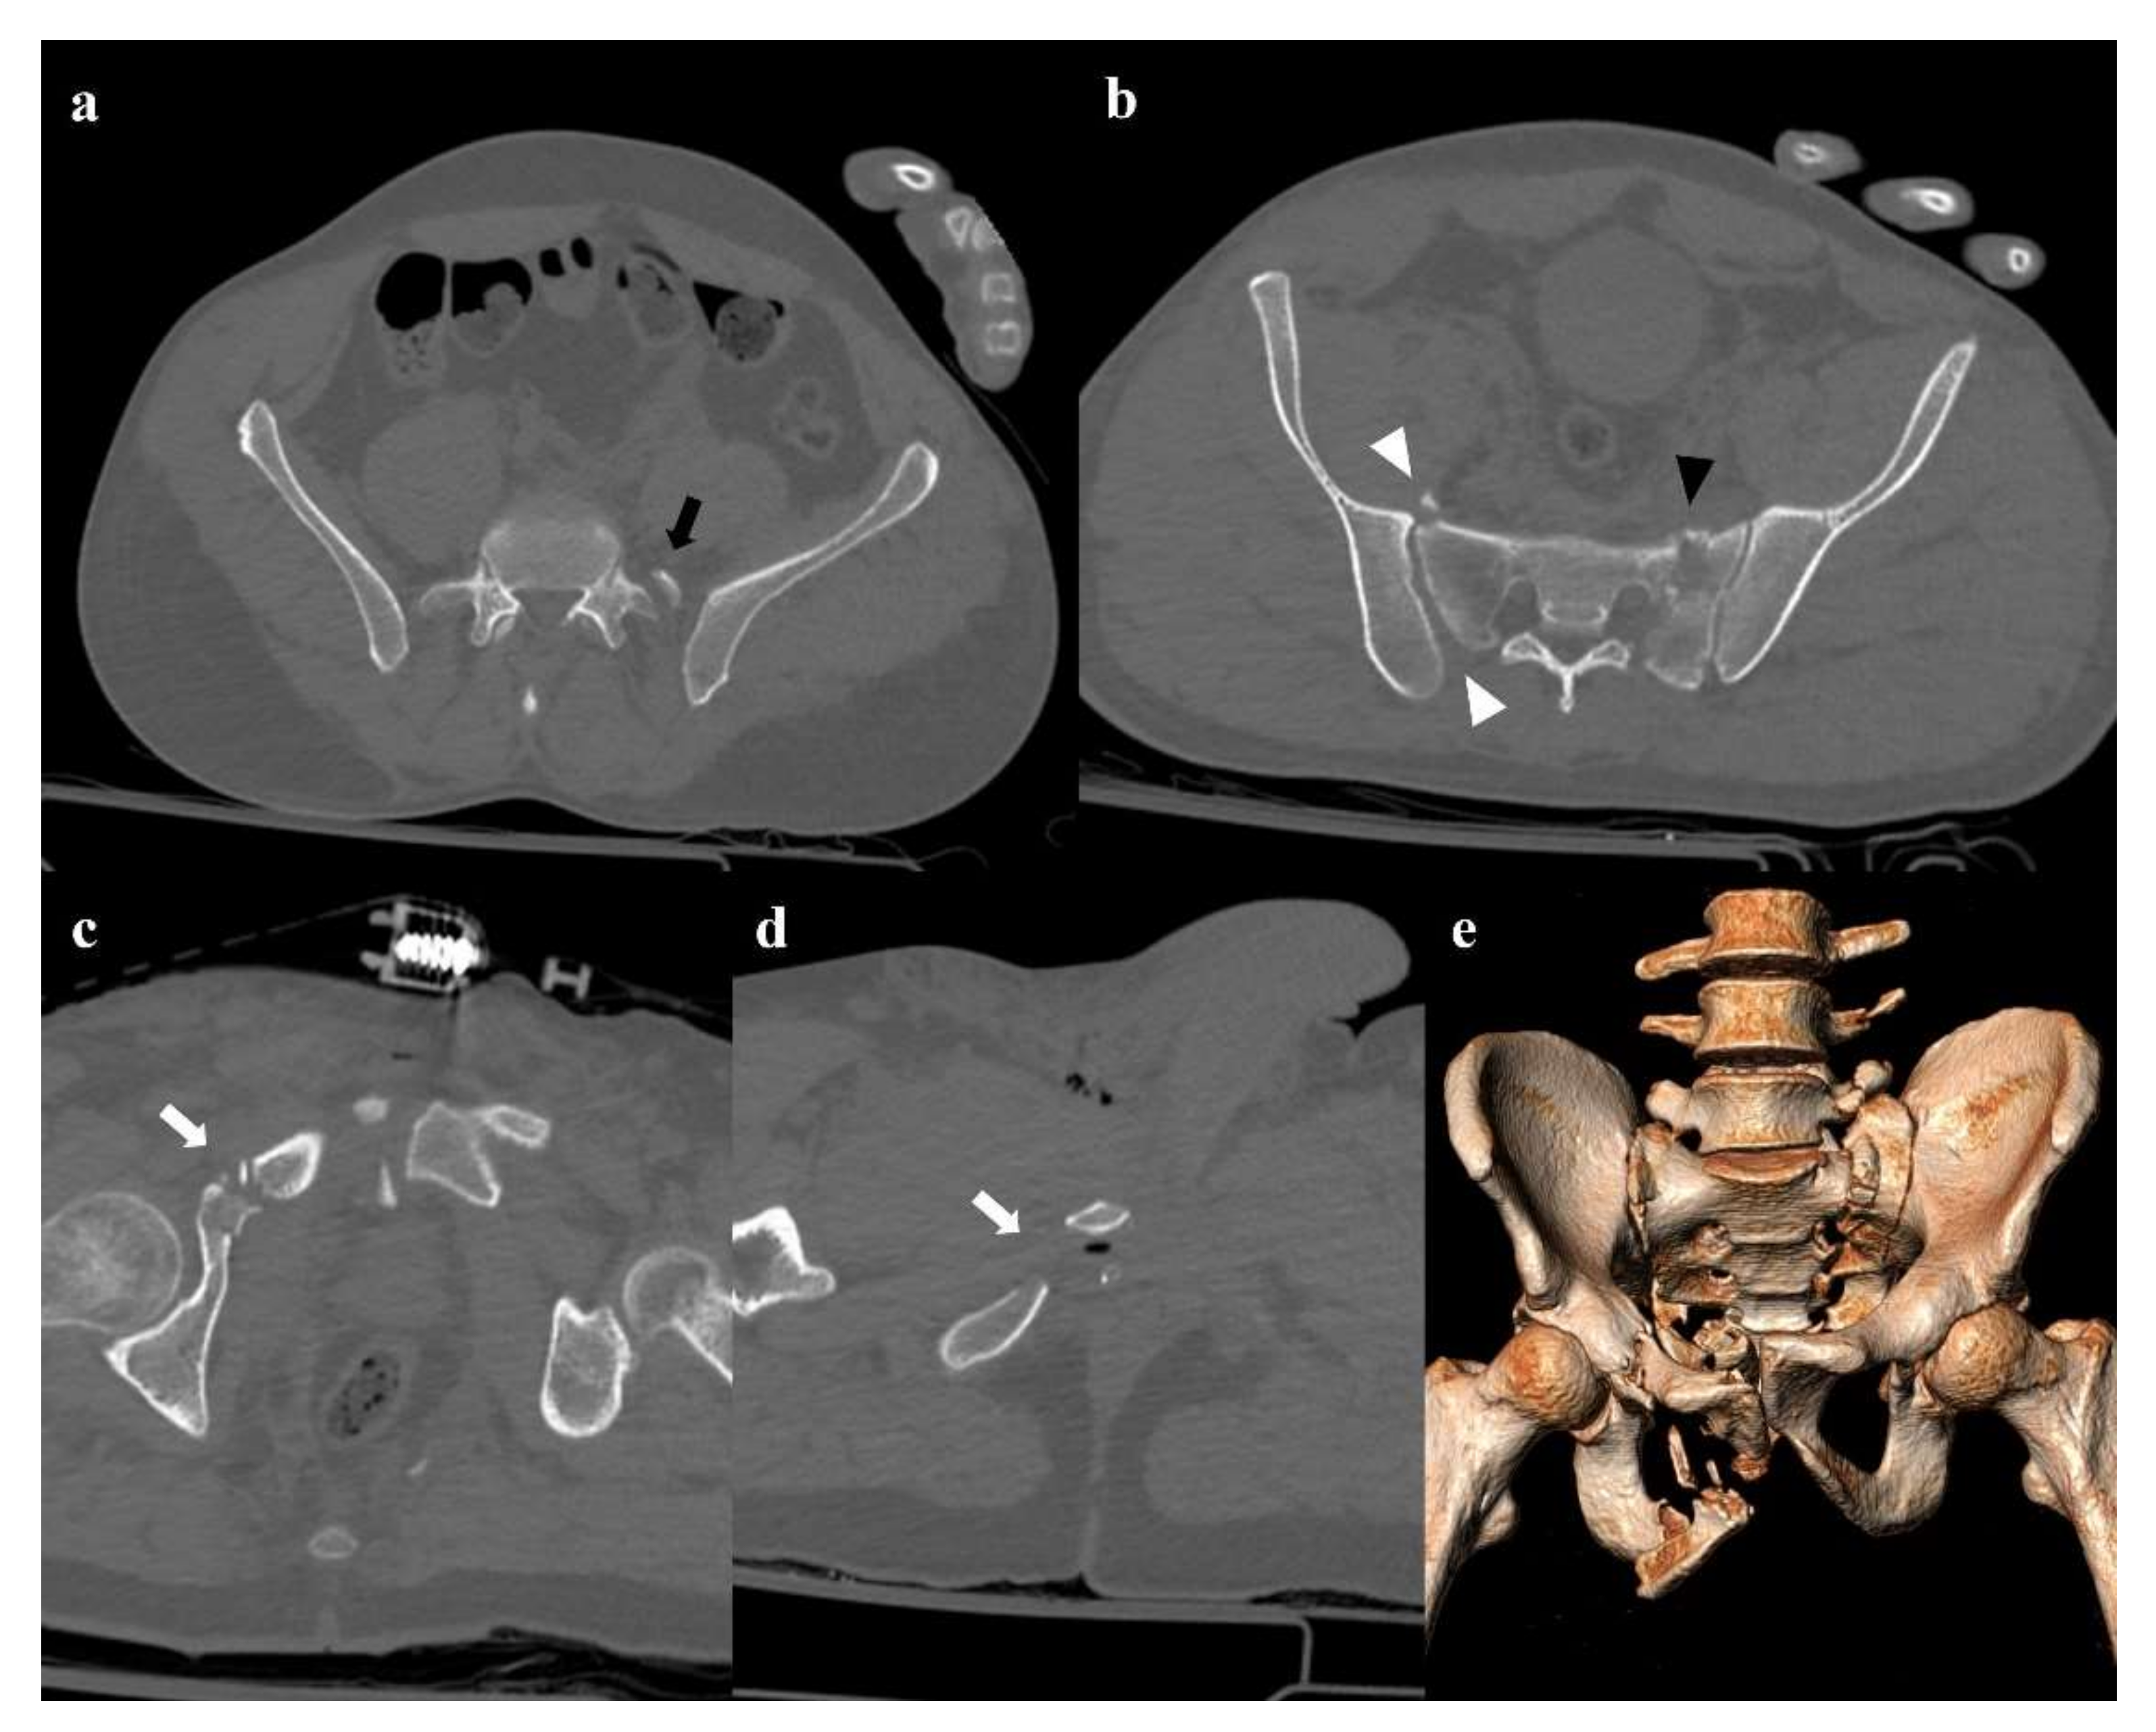

A force vector acting in the craniocaudal direction (typically, a fall from a height) can cause a destruction of the posterior elements of the pelvis and a cranial shift of the hemipelvis [13]. Involvement of the posterior arch of the pelvic ring is characterized by the avulsion of the transverse process of the fifth lumbar vertebra on the impact side, which is a sign of iliolumbar ligament rupture (Figure 7). Along the posterior arch, vertical shear injuries can also cause vertical fracture of the sacrum, sacroiliac diastasis, and iliac wing fracture. Anteriorly, this kind of trauma may show a disruption of the pubic symphysis and vertical fracture of the pubic rami. Rotational and vertical instability is the result of vertical shear injuries, that are also associated with vascular, genitourinary, and neurological complications [14]. Vertical shear injuries require a surgical fixation [3].

Figure 7. Vertical shear fracture. Axial CT images show avulsion of the left transverse process of the fifth lumbar vertebra (black arrow in (a)), fracture of the left side of the sacrum with involvement of the foraminal zone (black arrowhead in (b)), and fracture of the right superior and inferior pubic branches (white arrows in (c,d)). There is also a little fracture of the right wing of the sacrum, and a posterior widening of the right sacroiliac joint (white arrowheads in (b)). Three-dimensional volume-rendering CT reconstruction clearly depicts the instability of the pelvic ring, with the fracture of the left transverse process of the fifth lumbar vertebra and the cranial shift of the left hemipelvis (e).